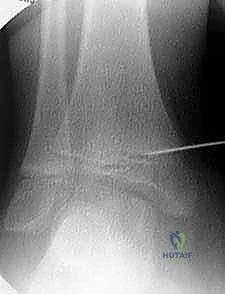

2. التصوير الشعاعي المتقدم:

لا يكتفي الدكتور هطيف بالفحص السريري، بل يتم إجراء صور أشعة سينية (X-rays) للقدم والكاحل أثناء وقوف الطفل (تحمل الوزن). يتم قياس زوايا دقيقة جداً لتقييم مدى الانحراف، مثل زاوية الساق والعقب (Tibiocalcaneal angle) وزوايا المفاصل الأخرى.

الخطوة الثانية: التوجيه بالأشعة التلفزيونية (Fluoroscopy)

يستخدم الدكتور هطيف جهاز الأشعة السينية المتحرك (C-arm) داخل غرفة العمليات لتحديد موقع الغضروف المشاشي (مركز النمو) بدقة متناهية بالملليمترات، دون الحاجة لفتح جراحي كبير.